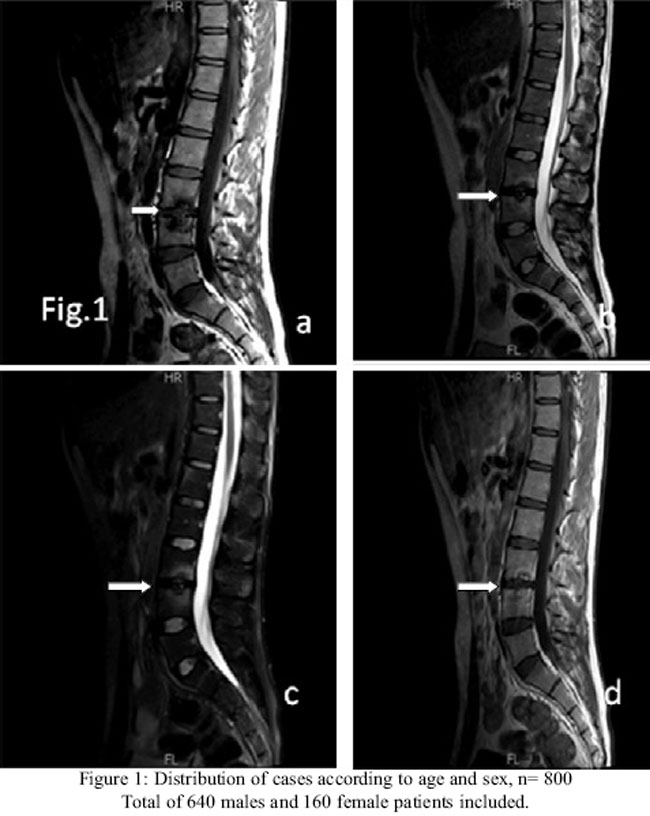

An MRI lumbar spine was done which showed abnormal signal intensity along the end plates of L3 and L4 vertebra with desiccation of intervening disc. Signal intensity was hypointense on T1-and hyperintense on T2 and fat saturation sequences. After administration of intravenous Gadolinium, these showed enhancement, as seen in Figure-1.

There was no evidence of epidural, prevertebral and paravertebral component. Based on these findings the diagnosis of Ankylosing Spondylitis (Andersson lesion) was suggested.